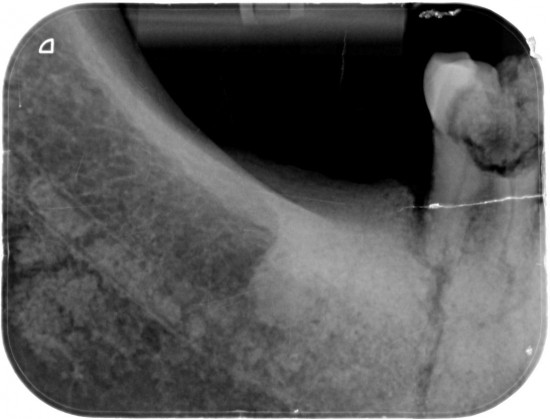

Van de M2 en de M1  (Links) werden  extra rontgenfoto,s gemaakt om  duidelijk te maken dat het niet een maar  twee aparte kiezen betrof .

Duidelijk zichtbaar de wortels van beiden tanden ..

Verder was goed zichtbaaar de vergaande  botontsteking bij de gebroken kiezen .